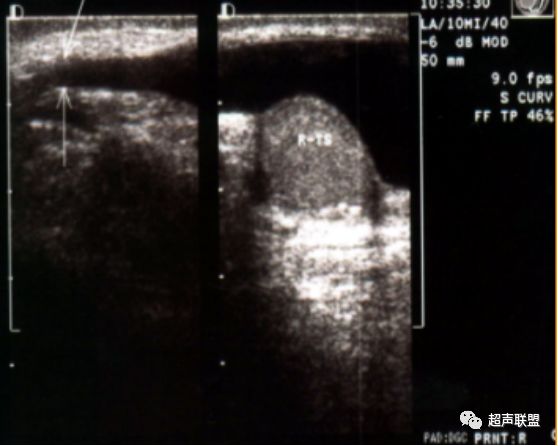

节段性睾丸梗塞 令人尴尬的 楔形 华斌的超声世界 二十次幂